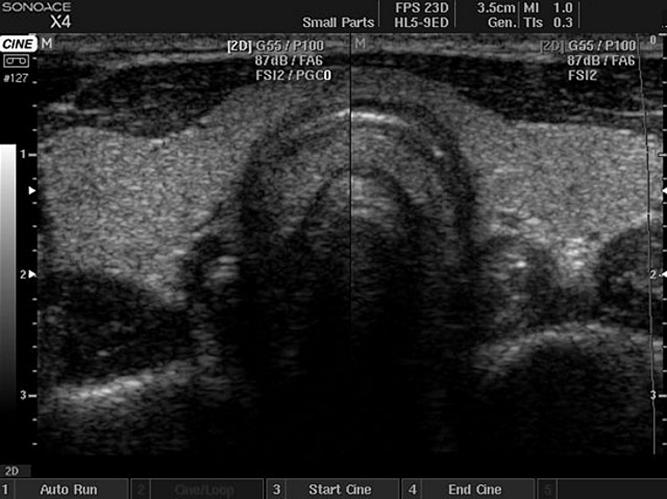

T1c — Непальпируемый рак простаты выявляется при биопсии под контролем ТРУЗИ; показания к проведению биопсии — высокий уровень ПСА;

II стадия: локализация опухоли только в предстательной железе. Однако по сравнению с I стадией опухоль выросла в размерах, и может быть диагностирована при пальцевом ректальном исследовании и с помощью УЗИ.

Материалом для исследования является ткань предстательной железы. На сегодняшний день с целью забора исследуемого материала предстательной железы используется тонкоигольная мультифокальная биопсия